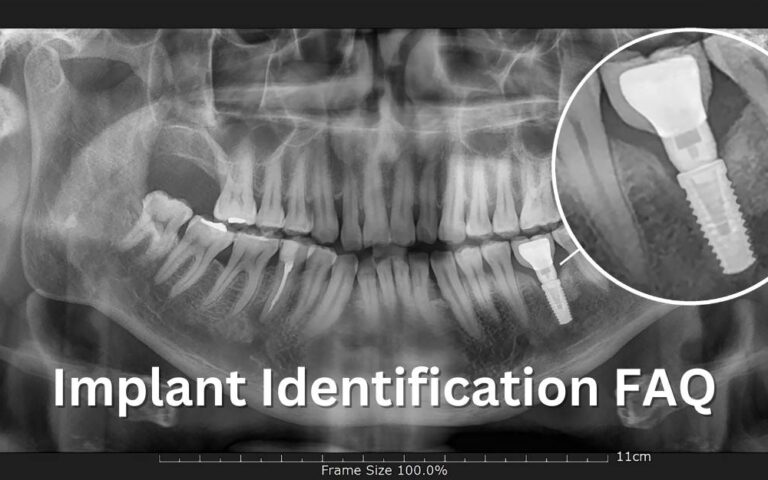

Your Implant identification guide to determine the brand, type, or size of an unknown dental implant before performing an implant mechanical rescue.

A Diagnostic and Treatment Algorithm for Fractured Implant Screw Retrieval: Organizing for a Safe Recovery to Preserve Implant Integrity.